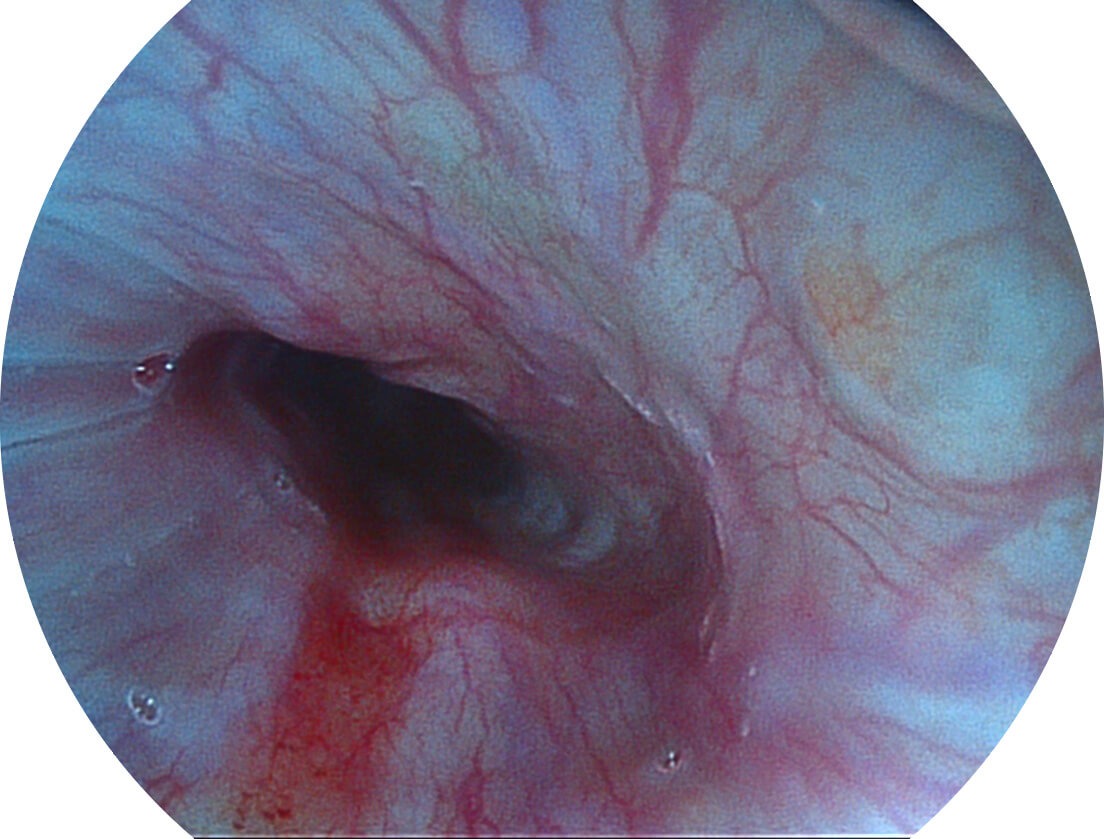

Spectral Focused lmaging, SFI

图像具有高亮度、高黏膜血管颜色对比度的特点,且不改变粘液、食物残渣、粪便的基本颜色,可在中远景下进行观察,助力消化道早期疾病的诊断。

SFI图像